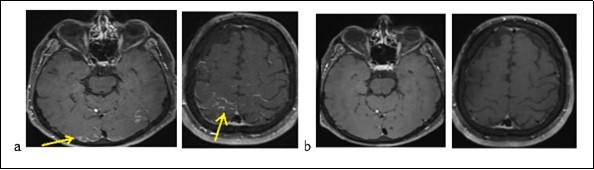

Mr. P.B., a man of 56, suffering from a left sudden hemiparesis within 30 minutes, was admitted to hospital on September 21, 2017. The beginning was marked by a feeling of head emptiness and unusual serious headache during a flight. This headache was followed by gradual paraesthesia of the left hemibody, moving from the vertex to the lower limbs. A left hemiparesis and speech disturbance resulted from paraesthesias. These symptoms decreased about 10 minutes. The plane had landed under an emergency condition and the patient was admitted to stroke emergency unity. There is a need to say that he had no history of vascular pathology before. On test, the result showed that blood pressure was 144/96 mm Hg. Consciousness of the patient was normal with good temporo-spatial orientation. Besides, Neurological test and other tools were normal. The routine biological test was normal too: the blood count, the C-reative Protein (CRP), blood urea, creatinine, ionogram, transaminases and gammaglutamyl transferases were normal. There was no abnomalies in the immunological assessment (antinuclear, anti cardiolipids, anti B2 GP1, circulating anti-body of lupus type, ANCA and native anti DNA). The serologies: Human immunodeficiency virus (HIV), Syphilis, Lyme, viral hepatitis C and B (HVC, HVB ) were negative. The cerebro-spinal fluid (CSF) was normal. A brain MRI (Figure 1a) displayed a cortical contrast enhancement in relation with possibly pial leptomeningeal involvement, some hypersignals on Flair sequences of frontal and parietal subcortical white matter. An assessment of pachymeningitis with a thoraco-abdomino-pelvic scanner and an electroencephalogram (EEG) were normal. The cerebral MRI (Figure 1b) after 8 days had shown a complete regression of the lesions. We noted that the diagnosis of an RPE syndrome facing the serious onset of symptoms, the MRI findings and the complete decrease of the lesions.

Figure 1.Brain MRI displaying occipital cortical hypersignals in Flair sequences (a) and decrease of lesions (b)